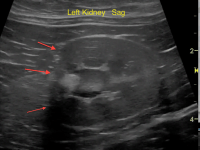

Ureteral Stricture in an asymptomatic cat